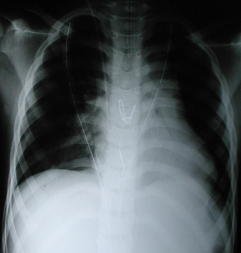

• Radiología Pos – Operatoria

• La radiografía pos-operatoria inmediata muestra un corazón en posición lateral izquierda, pero evidentemente centrado, dos tubos torácicos para drenaje mediastinico pleural bilateral fueron necesarios por abertura de ambas pleuras con exteriorización en el epigastrio, ademas, un drenaje aspirativo sub-pectoral.